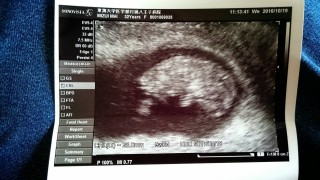

写真:9w6d:なぁぁさん

頚管が短いのと、脱落膜ポリープからの強出血で入院中です。

流産の覚悟もしてくださいと言われた時から、ポリープからの出血がとまり、なんとかまだ流産せず、赤ちゃんだけは元気に育っています。

今日初めて超音波でめちゃくちゃ動いてるのを見ました。まさしくダンシングベイビー!(知らない方は検索を)

ビックリしました。

頭の大きさも1cm とのことで順調に育っているらしいです。

動いたのを見てしまったら余計…ちゃんと産みたい。と思いました。

流産しないことを祈るばかりです!